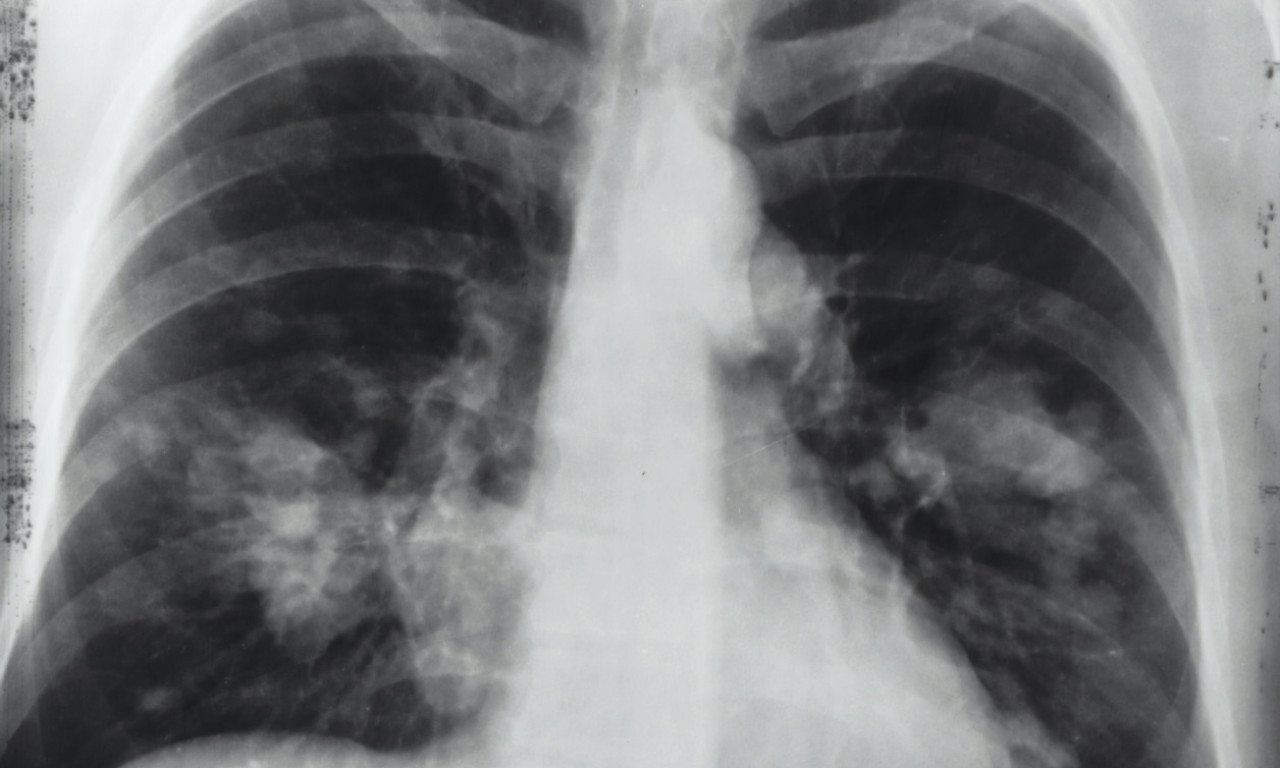

Foto: Shutterstock